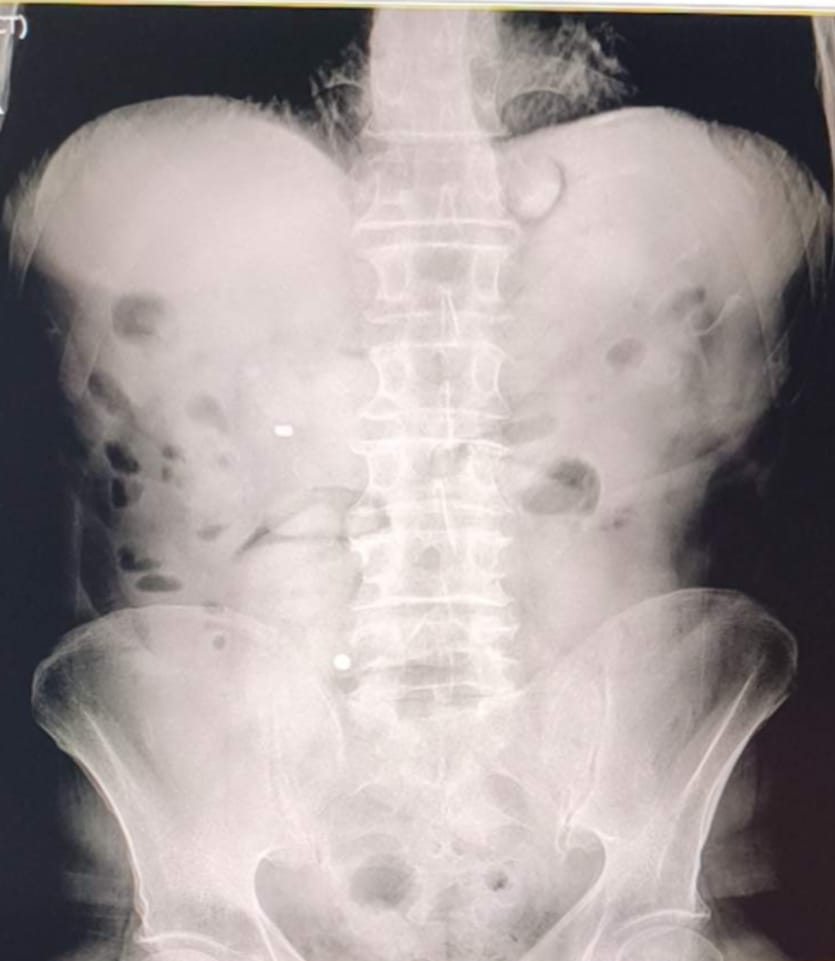

Şüphelilerin hastanede yapılan kontrolleri ve çekilen röntgen filmleri sonrası mide ve bağırsaklarında çok sayıda kapsül bulunduğu tespit edildi. Doktor gözetiminde sürdürülen tıbbi müdahale ve kontrollü süreç sonunda toplam 93 parça halinde 1 kilo 70 gram metamfetamin ele geçirildi. Operasyonun ardından gözaltına alınan iki şüpheli hakkında “Yasaklı veya Uyarıcı Madde Ticareti” suçu kapsamında adli işlem yapıldı. Emniyetteki işlemlerinin tamamlanmasının ardından adliyeye sevk edilen zanlılar çıkarıldıkları mahkemece tutuklanarak cezaevine gönderildi.